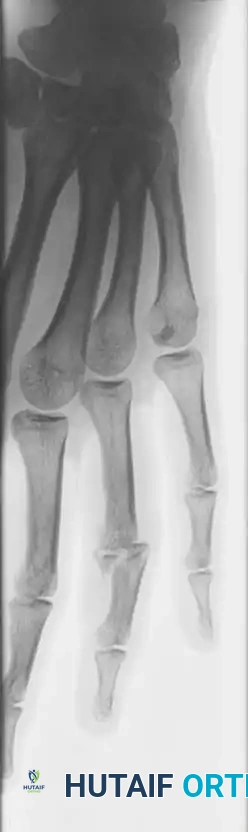

Fractures of the phalanges are among the most common skeletal injuries encountered in orthopedic and hand surgery. While many can be managed nonoperatively, unstable, displaced, or intraarticular fractures demand precise surgical intervention to restore the intricate biomechanical balance of the hand. The middle and proximal phalanges are particularly susceptible to direct blows on the dorsum of the fingers or axial loading combined with torsional forces.

Understanding the deforming forces is paramount. In proximal phalanx fractures, the intrinsic muscles (interossei and lumbricals) flex the proximal fragment, while the central slip of the extensor mechanism extends the distal fragment. This predictably results in volar angulation (apex volar), causing the fingers to assume a claw position.

Fractures of the Middle and Proximal Phalanx